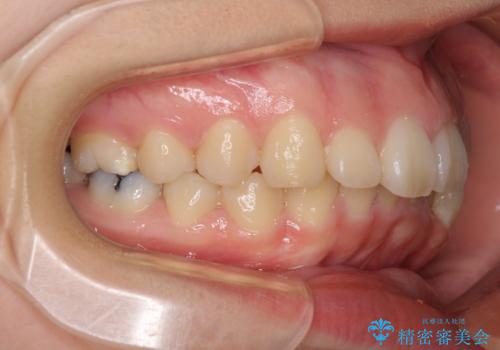

- 口元の突出感を気にして来院された患者様です。

上下左右の第一小臼歯4本を抜歯して口元を下げる治療計画としました。

非常に大きな虫歯のあった下顎大臼歯は、根管治療を行い、矯正治療後にオールセラミッククラウンにて補綴治療を行いました。